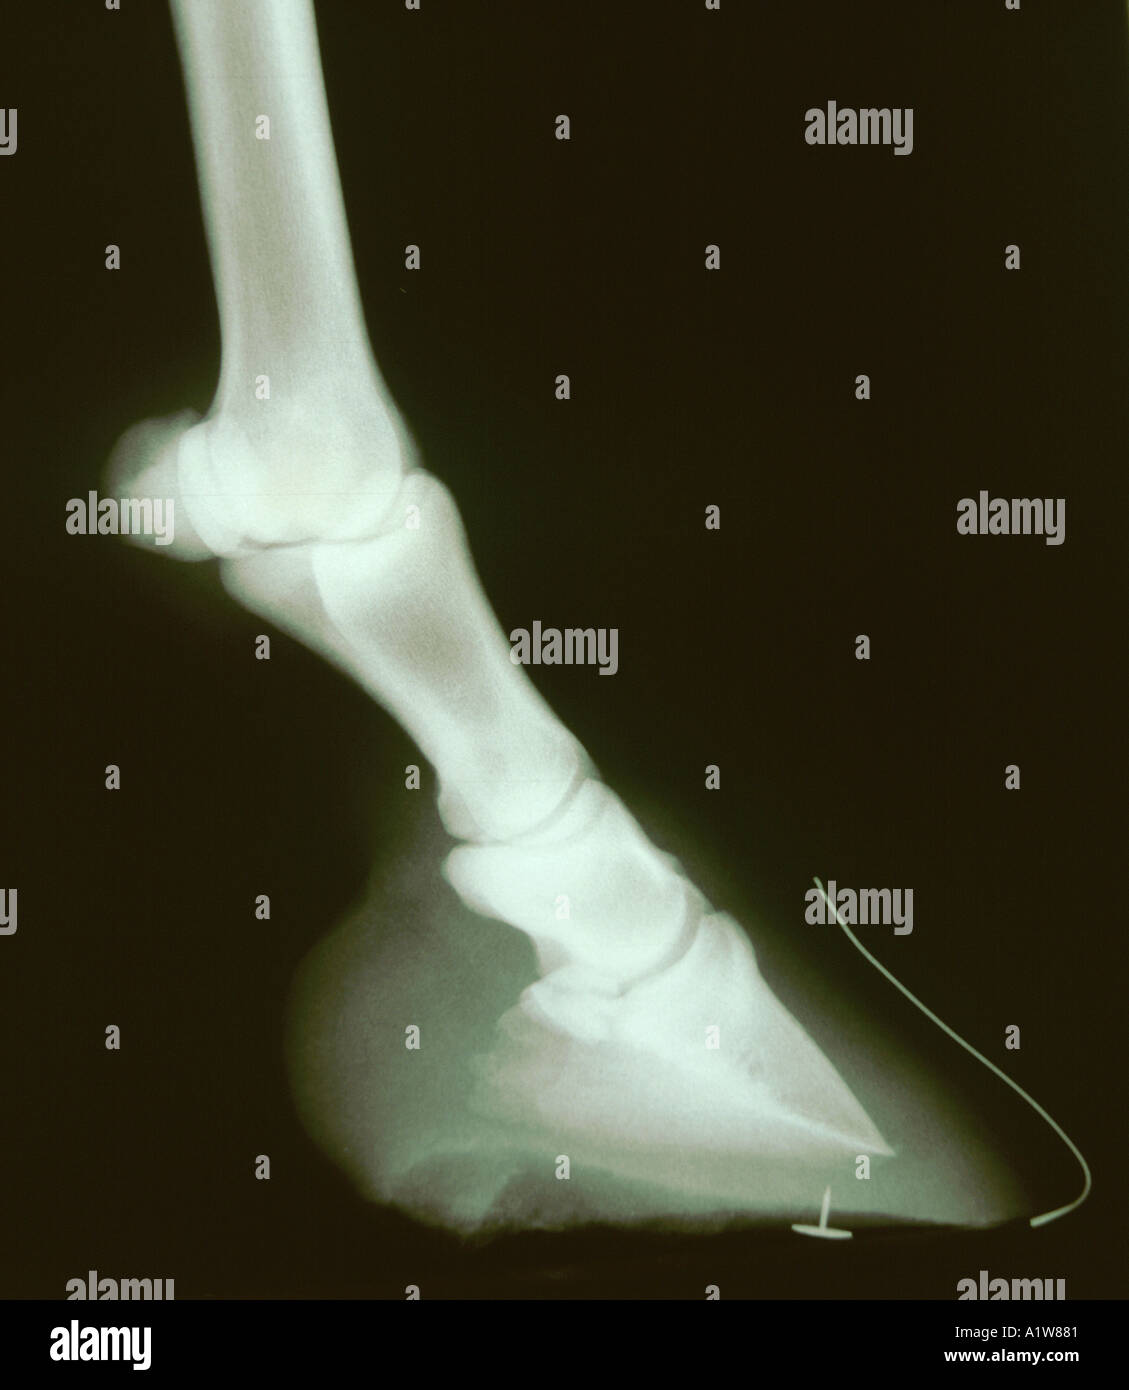

From www.alamy.com

X ray of horses hoof showing wire markers to assess rotation of pedal Horse Hoof X Ray Cost a veterinarian explains why hoof radiographs are important, how to use them, and what role they play in helping. Your horse may need to be sedated, depending on their temperament, to ensure the best quality image. i paid nearly £1000 for a lameness check and x rays of hocks, stifles and an ultrasound of the suspensories. Computed tomography. Horse Hoof X Ray Cost.